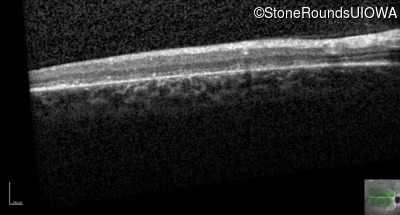

AR Stargardt Disease (IIA)

AR Stargardt Disease (IIA)

| Age at visit: 12 years |

| Age at visit: 13 years |

| Age at visit: 15 years |